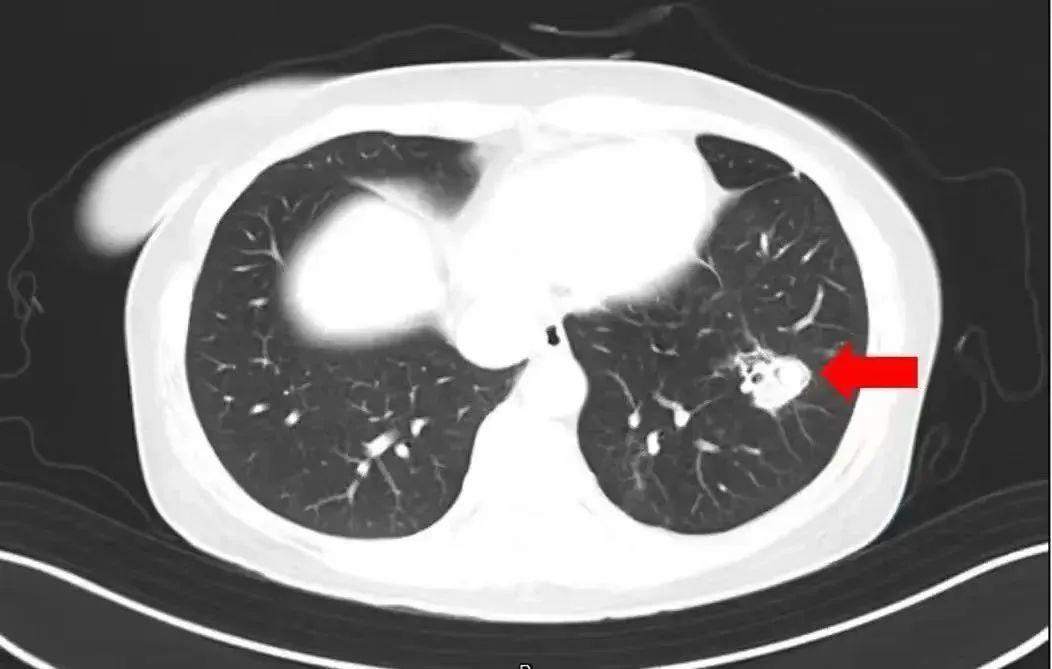

医生通过问诊了解到,沈女士在整理衣柜时发现里面长了霉斑,于是对衣柜做了清理,但清理时没戴口罩。为进一步确诊病情,医生为沈女士进行纤维支气管镜检查及肺泡灌洗液病原体检测,果然发现气道壁上有大量白色菌斑,化验后确认是曲霉菌。